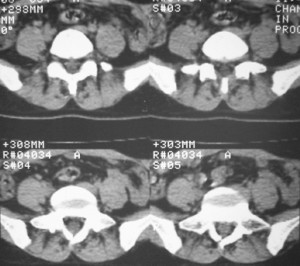

标题: CT7246: F,30岁,下腰痛,同事的片子,请老师们看看,初 [打印本页]

标题: CT7246: F,30岁,下腰痛,同事的片子,请老师们看看,初

典型的致密性髂骨炎

典型的双侧骶髂关节致密性骨炎.

致密性骨炎,好发于骶髂关节的髂骨侧的耳状面(少见部位有骶骨,耻骨联合,甚至锁骨也有报道),好发于育龄期的妇女,多对称发病

何谓髂骨致密性骨炎?髂骨致密性骨炎是发生于髂骨耳状关节部分的骨质密度增高性疾病。病因迄今不明,可能与妊娠、机械性劳损、病灶性炎症有关。本病好发于20~35岁的育龄妇女,偶见男性。

髂骨致密性骨炎的临床表现与体征:腰骶部疼痛,多呈慢性、间歇性酸痛、隐痛,可向一侧或双侧臀部及大腿后侧扩散,但不沿坐骨神经方向放射,步行、站立、负重及劳累后加重,咳嗽、打喷嚏不能使疼痛明显加重,休息后症状减轻。患者腰骶角加大,局部有压痛和肌紧张,骨盆分离和挤压试验阳性,“4”字试验阳性,化验检查多在正常范围内。x线检查,骶髂关节间隙整齐清晰,靠近骶髂关节面中的髂骨耳状关节部分骨质密度增高,呈均匀浓白边缘清晰的骨质致密带,骨小梁消失,无骨质破坏。本病应注意与早期强直性脊柱炎、骶髂关节结核相鉴别。